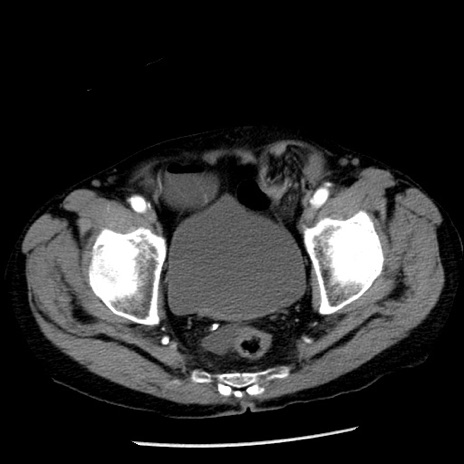

症例26(横断像)

【症例】80歳代男性

【主訴】嘔吐

【現病歴】昨晩2回嘔吐あり、今朝になっても嘔吐あり。来院。

【既往歴】胃潰瘍

【身体所見】意識清明、BT 37.6℃、BP 166/95mmHg、HR 100bpm、SpO2 97%、腹部:平坦・軟、腸蠕動音聴取良好、圧痛なし。

【データ】WBC 21900、CRP 1.46